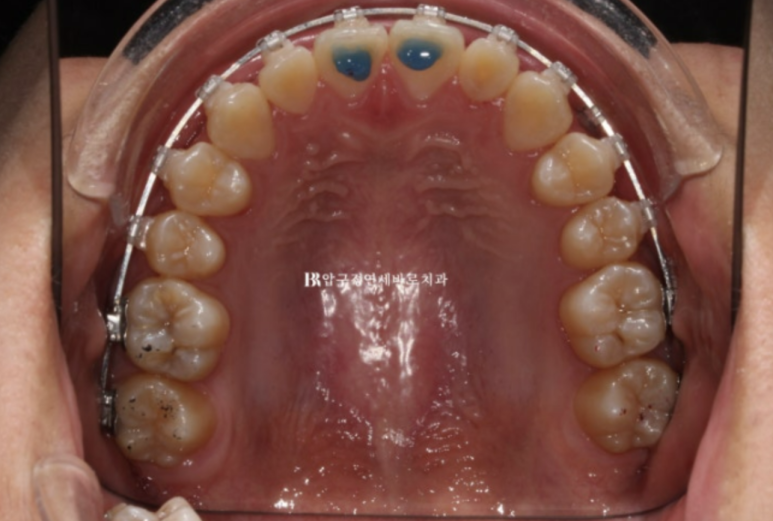

23.07

앞니에 파란색 레진 부분 바이트 블럭을 올려서 과개교합 개선과 소구치 정출을 도모했습니다.

23.11

전체치료기간은 1년 1개월입니다.

환자분 나이가 어린 편이라 빠르게 마무리가 잘 되었습니다.